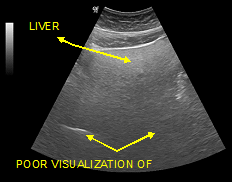

The fatty infiltration of the liver is shown on ultrasound with significantly increased echogenicity "bright liver", in comparison with the right kidney cortex (Figure 1). Normally, the liver and the renal cortex have similar echogenicity, relative to the parenchyma of the pancreas and the spleen. The maximum diameter of the liver in the midclavicular line (MCL) was increased, right lobe>15 cm (Figure 5). Also significant features are the absence of mass effect on intrahepatic vasculature (Figure 6) as well as the poor visualization of the deep parts of the liver (Figure 7), due to decreased permeability of the acoustic beam. A focal or diffuse morphology has been shown to increase the echogenicity of the fatty liver. Differential diagnosis is caused by focal fat infiltration (Figure 8), which has a geographic distribution. In this case, hypoechoic areas correspond to normal hepatic parenchyma on fatty infiltration sites, whereas, normal parenchyma islets can easily be identified due to their typical positions, in front of the right branch of the portal vein, its division, around the area of the gallbladder and the caudate lobe.9−13

Figure 6 Deafness of intrahepatic vessels in fatty infiltration.

Figure 7 Poor visualization of the deeper parts of the organ and inability visualization of the diaphragm. (Grade III of fat filtration).